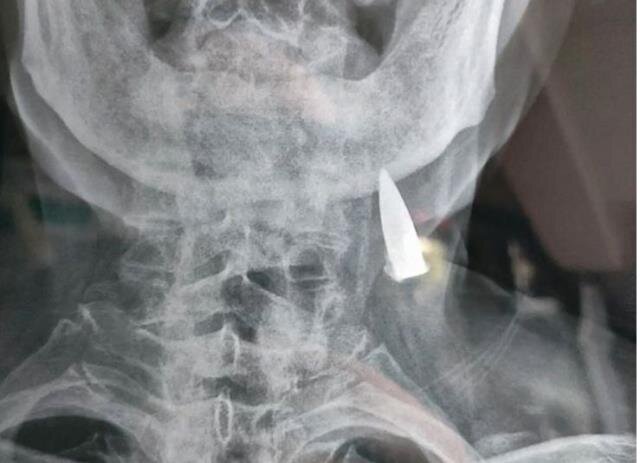

Baş ağrısı şikayəti ilə həkimə gedən 95 yaşlı kişinin rentgen nəticələri həkimləri şoka saldı

AZXEBER.COM xarici mediaya istinadən xəbər verir ki, 95 yaşlı Zhao He baş ağrısı şikayəti ilə getdiyi xəstəxanada rentgen çəkdirib.

Nəticələri alan həkimlər gördükləri detala heyran qalıblar. Kişinin boynunda bir güllə tapan həkimlər bu güllənin 70 ildir kişinin boynunda olduğunu müəyyən ediblər.